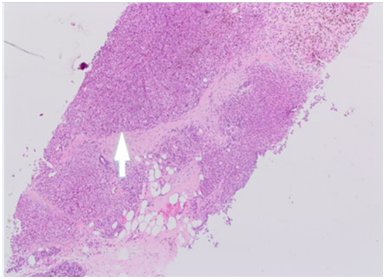

A 43years old white premenopausal female patient admitted though Emergency Department with a recent history of unwell feeling in addition to sudden onset of dizziness, ataxia, vomiting & loss of vision on right eye. Initial clinical assessment revealed loss of coordination, as well as blind right eye and partial unilateral deafness. The patient partner pointed to a smaller pigmented nevus in the anterior chest wall which started to be darker recently. Clinically, there is bilateral indeterminate scattered breast modularity and a small breast lump at the outer upper quadrant of the right breast measures about 30mm. Mammogram and breast US showed bilateral scattered irregular hypo echoic suspicious lesions measures between 5mm & 20mm , graded as M4U4. [BI-RADS: Breast Imaging Reporting and Data System]. A core biopsy was taken from the largest lesion in the right breast (Figure 1) (Figure 2).

Figure 1 A: CC View, B: MLO View.

CC (Cranial-Caudal) & MLO (Medio-lateral-oblique) views of right mammogram indicating 17mm suspicious lesion in the OUQ (Outer Upper Quadrant).